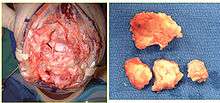

Articular surface

The articular joint's surface must be smooth for it to function properly. Irregularity may result in radiocarpal arthritis, pain, and stiffness. More than 1 mm of incongruity places the patient at a high risk for post-traumatic arthritis. Significant articular incongruity typically occurs in young patients after high energy injuries (Figure 2). If the surface is very irregular and cannot be reconstructed, then the only option may be a fusion.

Surgery

Contemporary surgical options have improved treatment of this injury. Techniques include Open Reduction Internal Fixation (ORIF), external fixation, percutaneous pinning, or some combination of the above. Significant advances have been made in operative open reduction and internal fixation. Two newer treatment are fragment specific fixation and fixed angle volar plating. These attempt fixation rigid enough to allow almost immediate mobility, in an effort to minimize stiffness and improve ultimate function, although there has been no demonstration of improved final outcome from early mobilization (prior to 6 weeks after surgical fixation). Although restoration of radiocarpal alignment is thought to be of obvious importance the exact amount of angulation, shortening, intra articular gap/step which impact final function are not exactly known. The alignment of the distal radioulnar joint is also important as this can be a source of a pain and loss of rotation after final healing and maximum recovery.

An arthroscope can be used at the time of fixation to evaluate for soft tissue injury. Structures at risk include the triangular fibrocartilage complex and the scapholunate ligament. Scapholunate injuries in radial styloid fractures where the fracture line exits distally at the scapholunate interval should be considered. TFCC injuries causing obvious DRUJ instability can be addressed at the time of fixation.